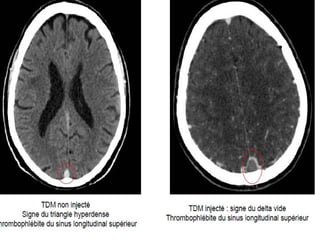

TVC : SCANNER CEREBRAL

• Signes directs : hyperdensité avant injection

(SLS, SL, sillon cortical)

delta vide après injection (SLS)

• Signes indirects : œdème cérébral, hématome

TVC : SCANNERCEREBRAL • Normal dans 30 % des cas • Peut éliminer autres causes • Signes directs : hyperdensité avant injection (SLS, SL, sillon cortical) delta vide après injection (SLS) • Signes indirects : œdème cérébral, hématome